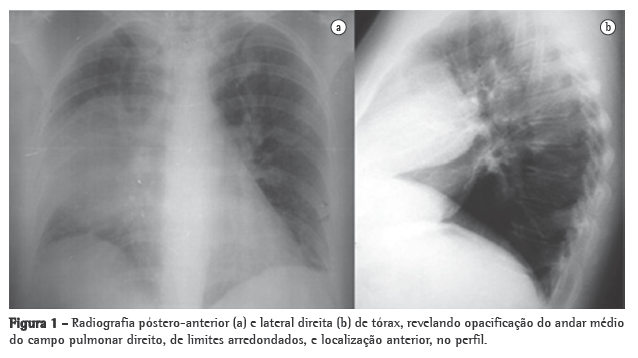

Apresentava também hipoxemia ao ar ambiente (PaO2: 79,5 mmHg) e ligeira hipocapnia (33 mmHg). A radiografia do tórax revelou uma opacidade no terço médio do campo pulmonar direito (Figura 1).

A radiografia do tórax foi repetida no 8º dia de internamento, mostrando persistência da opacidade já descrita. Para um melhor esclarecimento realizou-se, então, uma TC torácica, que revelou uma formação sólida, no mediastino anterior, com 10 cm no maior diâmetro, com planos de clivagem com o coração e o pulmão, insinuando-se entre os lobos pulmonares e comprimindo-os. Realizou-se também uma ressonância magnética para um melhor esclarecimento dos limites da lesão, nomeadamente no que se refere ao plano de clivagem com as estruturas do mediastino (Figura 2), que confirmou as imagens da TC.